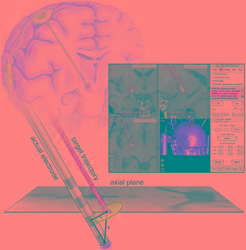

| Abstract | Intraoperative brain deformation is one of the most important causes affecting the overall accuracy of image-guided neurosurgical procedures. One option for correcting for this deformation is to acquire three-dimensional (3-D) ultrasound data during the operation and use this data to update the information provided by the preoperatively acquired MR data. For 12 patients 3-D ultrasound images have been reconstructed from freehand sweeps acquired during neurosurgical procedures. Ultrasound data acquired prior to and after opening the dura, but prior to surgery, have been quantitatively compared to the preoperatively acquired MR data to estimate the rigid component of brain shift at the first stages of surgery. Prior to opening the dura the average brain shift measured was 3.0 mm parallel to the direction of gravity, with a maximum of 7.5 mm, and 3.9 mm perpendicular to the direction of gravity, with a maximum of 8.2 mm. After opening the dura the shift increased on average 0.2 mm parallel to the direction of gravity and 1.4 mm perpendicular to the direction of gravity. Brain shift can be detected by acquiring 3-D ultrasound data during image-guided neurosurgery. Therefore, it can be used as a basis for correcting image data and preoperative planning for intraoperative deformations. |